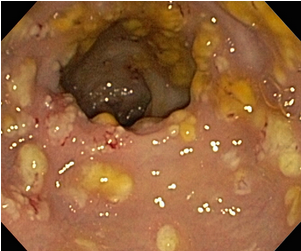

A 50-year-old female is hospitalized for a course of intravenous clindamycin to treat an abscess. Four days later she develops a watery diarrhea, with > 3 stools/day. Temperature is 102.2°F (39°C). Physical exam reveals abdominal tenderness with no guarding. Her WBC was 15,000 mm³ and she had a positive fecal leucocyte test. Sigmoidoscopy reveals 0.2 - 2 cm raised adherent yellow plaques.

pseudomembranous enterocolitis.

mucosal surface of the colon is hyperemic and is partially covered by a yellow-green exudate. The mucosa itself is not eroded. Broad spectrum antibiotic usage (such as clindamycin) and/or immunosuppression allows overgrowth of bacteria such as Clostridium difficile to cause this appearance.

Microscopically, the pseudomembrane is seen to be composed of inflammatory cells, necrotic epithelium, and mucus in which the overgrowth of microorganisms takes place. The underlying mucosa shows congested vessels, but is still intact